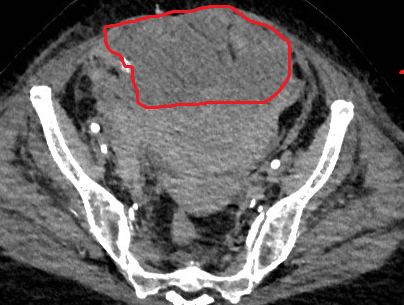

CT. Σημαντικό αιμάτωμα εκτεινόμενο στον προκυστικό χώρο (Ευγενική παραχώρηση Dr. V. Penopoulos).